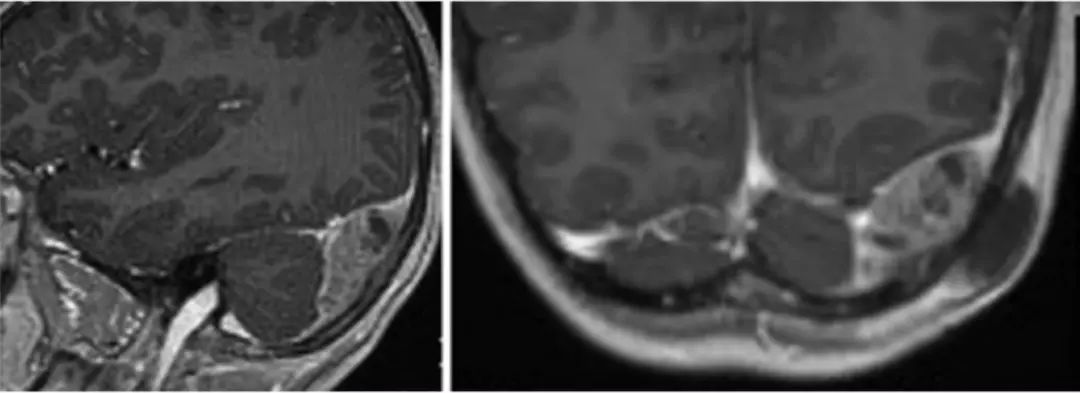

纳入的237例患儿中,94例女性,143例男性;平均年龄39个月;均诊断为神经母细胞瘤并行相关治疗。其中,5例(2.1%)患儿因脑内转移,接受开颅手术(图1、2)。颅内转移平均发生于首次诊断后的46个月,属神经母细胞瘤第4期。手术指征为颅外肿瘤治疗后出现颅内转移、或开颅治疗后颅内病灶进展伴神经功能障碍。术中发现,肿瘤与周围组织界限尚清晰,但也有浸润邻近组织。术后总生存期平均22个月。另有3例患儿发生颅内肿瘤脑外转移,同样接受手术治疗。

图2. 14岁女性,术前MRI矢状位(左)和轴位(右)成像示左枕部肿瘤。